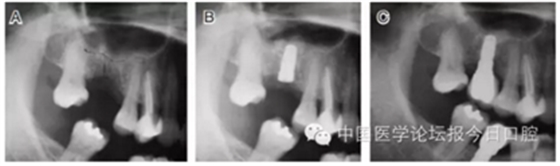

病例2 骨質(zhì)較少(圖4)

圖4